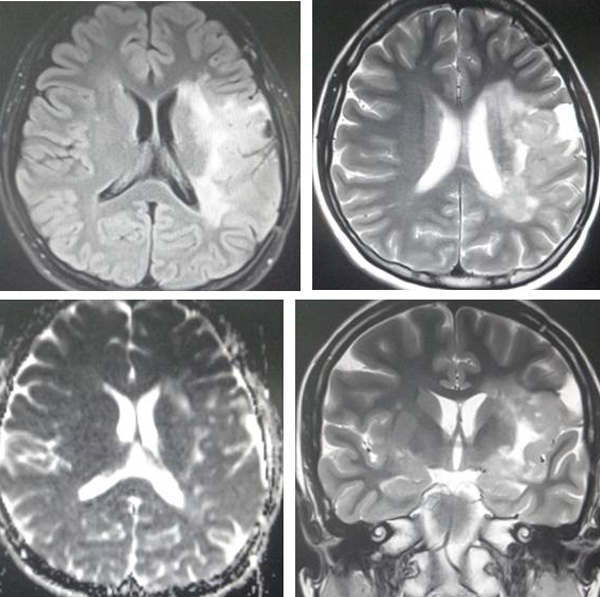

A CT scan on 30 October 2013 showed:

- Multiple enlarged mediastinal and right hilar lymph nodes.

- Numerous small nodules in both lungs – likely metastases.